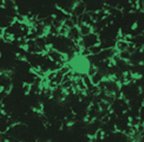

When the brain is injured or infected, cells called microglia leap into action. A new study indicates that these cells, which researchers previously had thought were quiescent in life’s less-stressful moments, are constantly sweeping their surroundings for signs of danger.